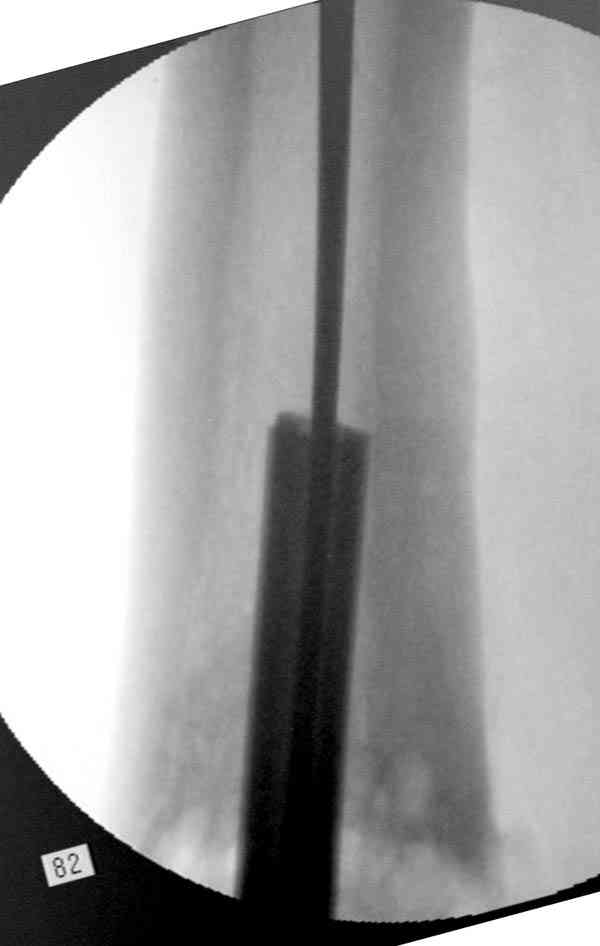

Сросшаяся малоберцовая как распорка привела к образованию ложного сустава. В таких случаях удаляем сломанный штифт и проводим стимуляцию ложного сустава рассверливанием. Рассверливание канала создает стимуляцию на месте ложного сустава, и динамический вариант блокировки штифта с большим диаметром создаст стабильность. Ранняя нагрузка после остеотомии малоберцовой приведет к сращению ложного сустава.

Приспособление для удаления сломанных штифтов и наличие ЭОП облегчит задачу. При отсутствии крючка тогда можно применить обычный длинный ball pointed guide wire от интрамедулярного набора. Проволока, пропущенная за пределы гвоздя и зажатая другая вытащат сломанный конец штифта без проблем.